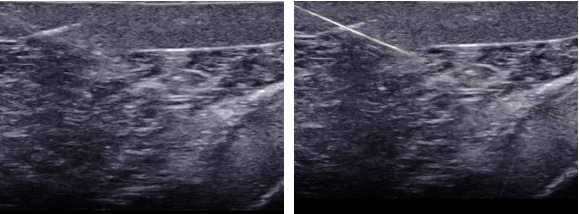

介入超声是在超声引导下将穿刺针、导管等医疗器具准确的进入靶目标从而达到诊断和治疗的一种手术手段,介入超声包括细针穿刺活检(FNA)、置管引流、囊肿硬化、结节的热消融。超声引导下穿刺介入手术就是在超声仪器检测下可直接观察到病灶目标,定位后将穿刺针对准靶目标后进行抽吸,如抽取肿瘤的实质是行组织或细胞的活检,胸水、腹水抽吸是实行抽液治疗。穿刺方法分为平面内穿刺和平面外穿刺,平面内穿刺是指沿探头长轴方向的穿刺A图所示,平面外穿刺是指探头短轴上的穿刺B图所示。

甲状腺FNA.jpg

甲状腺FNA过程图

A平面内穿刺                                  B平面外穿刺